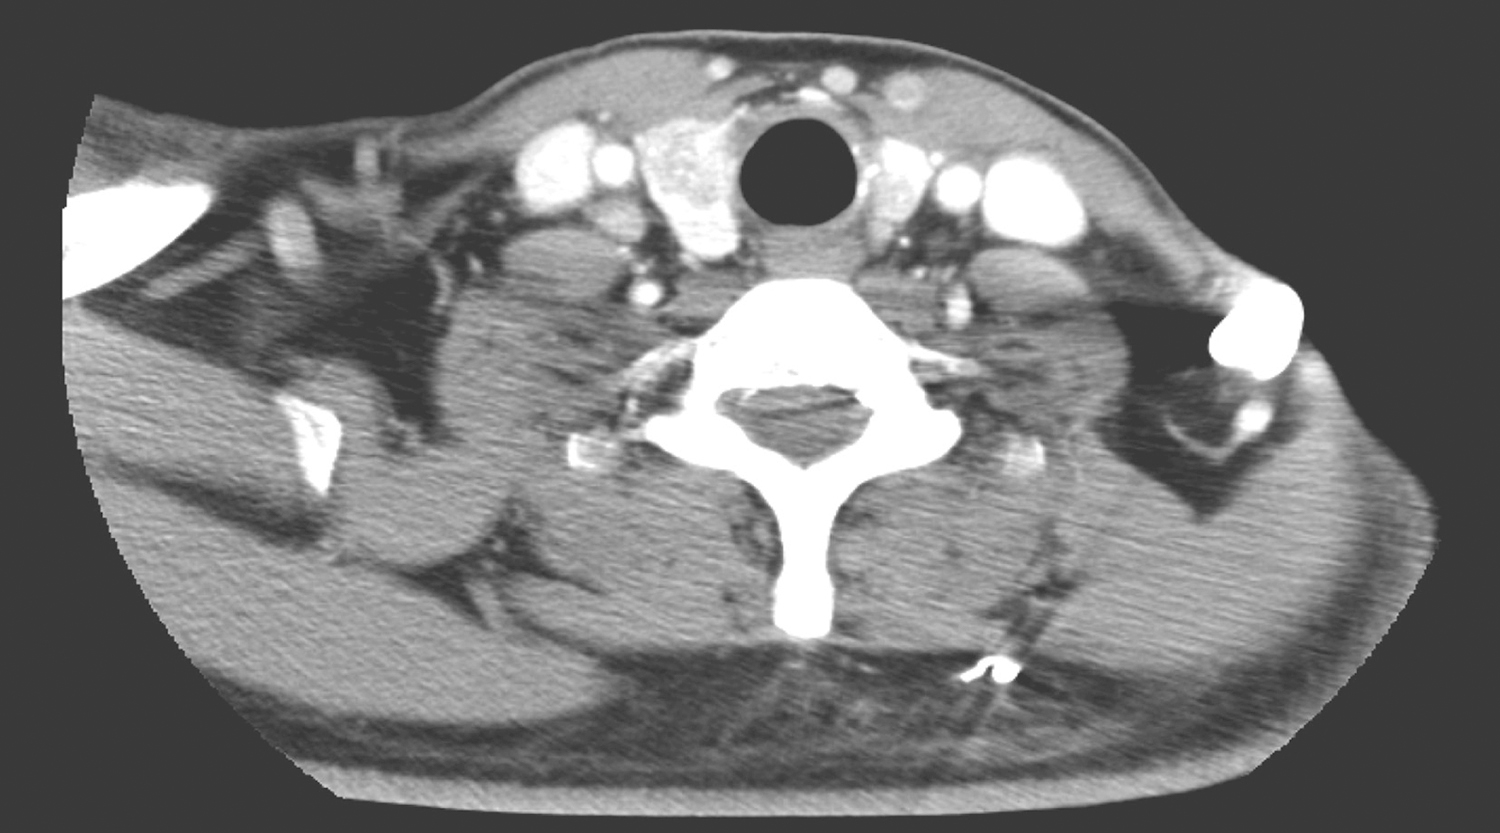

2.2013年10月10日,颈胸部CT检查所见:甲状腺左右叶内可见低密度结节,大者位于右叶,约1.6cm×1.2cm,其内可见高密度灶(图3)。扫描范围内鼻窦、鼻咽、口咽未见明确异常。

双颈深、右下颈甲状腺旁、双侧锁骨上、气管前、可见多发淋巴结肿大,部分明显强化,大者约1.2cm×0.9cm(图4~图6);余颈未见明显肿大淋巴结。

图3 颈部CT示甲状腺左右叶内低密度结节

图4 颈部增强CT示右颈肿大淋巴结